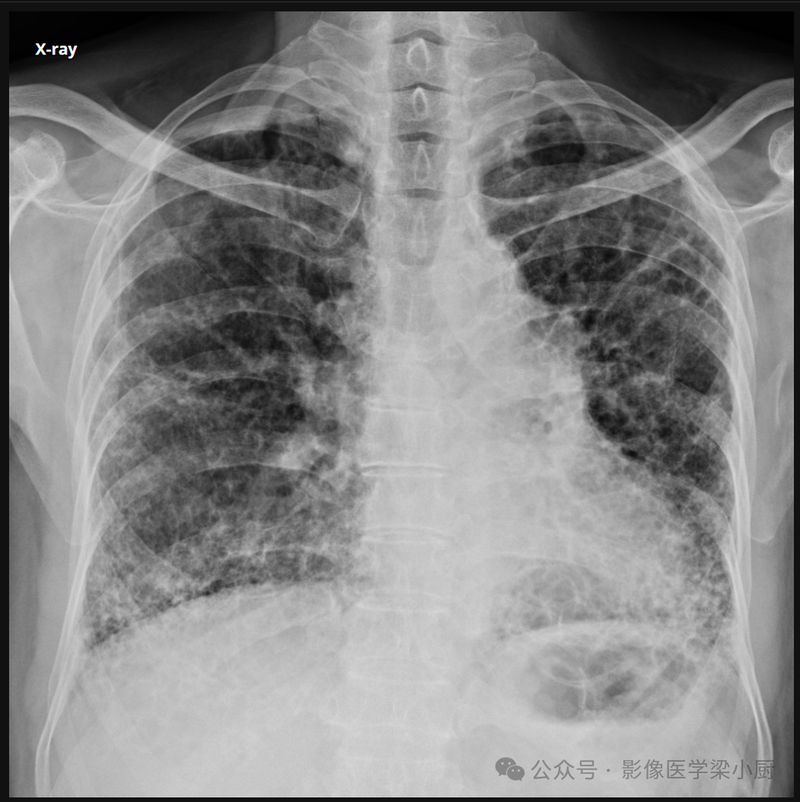

X线:

病变分布较广泛,好发于两肺门区附近及肺下野。病变累及支气管及血管周围的间质时,可见纤细条纹状密度增高影,边界清楚或略模糊,其走行僵直,可数条相互交错或两条平行。病变累及终末细支气管以下的肺间质时,病变显示为短条状,相互交织成网状的密度增高影,其内可见间质增厚所构成的大小均匀而分布不均匀的小结节状密度增高影。有时肺野内可见广泛的细小结节状影,大小一致,分布不均,但肺尖及两肺外带常不受累及。由于肺门周围间质的炎症浸润以及肺门淋巴结炎,可引起肺门影增大,密度增高,但结构不清。